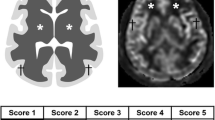

VOI measurement

The iplan RT Image 4.1 2 (BrainLAB) was used for VOI measurements. VOI measurements included 158 patients (70 GBMs, 29 atypical PCNSLs, and 59 typical PCNSLs). Post-contrast Axial CET1WIs were used to measure the whole tumor and non-enhancing area volume. The ROI was manually delineated layer by layer along the inner/outer margins of the visible tumor, as reported in the study by Wu et al [22] to further generate a 3D-ROI and obtain the volume of the nET, whole tumor (wT), and the ratio nET/wT, as shown in Fig. 3.

Given that all 158 cases (70 GBMs, 29 atypical PCNSLs, and 59 typical PCNSLs) showed obvious enhancement, enhancing and non-enhancing volumes were regarded as the tumor volume. Previous studies reported [8] that there was no significant difference in tumor volume between PCNSL and GBM. Our study showed that the tumor volume of both atypical PCNSL and all PCNSL groups is significantly smaller than that of the GBM group, which is consistent with previous studies [19]. We found that, compared with GBM patients, atypical PCNSL patients showed a significantly lower nET volume ratio. Choi et al [11] used the semiautomatic signal intensity threshold to calculate an optimal cut-off necrosis ratio of 13% for differentiating PCNSL and GBM. A recent study [22] used the RadioFusionOmics (RFO) model to differentiate between GBM and solitary brain metastasis, which included the volume of the non-enhancing and enhancing tumor and peritumoral edema. In this study, we attempted to differentiate atypical PCNSL patients from GBM patients using nET volume quantification. Youden’s index showed that an optimal cut-off nET volume ratio of 25% can be used to distinguish between atypical PCNSL and GBM. Although the study included atypical PCNSL (hematology, necrosis, or heterogeneous contrast enhancement), the nET volume ratio of the atypical PCNSL (14.9%) was significantly lower than that of GBM (30.8%). The possible reason is that GBMs are highly heterogeneous at molecular and histological levels with the tissue, including extensive pseudopalisading necrosis and microvascular proliferation [23].